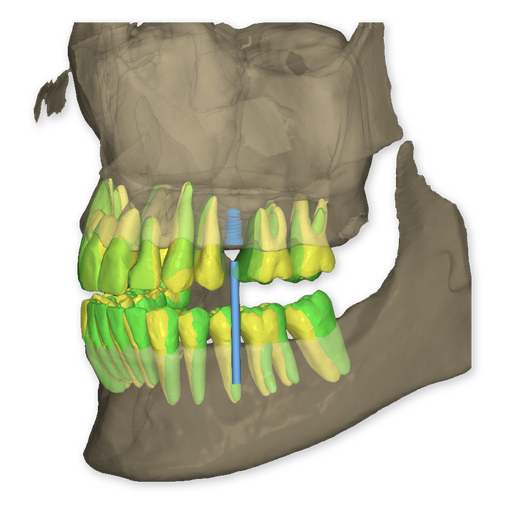

The DSD Interdisciplinary is a digital wax up of the upper and lower arches, designed considering a facially-driven, clinical and functional analysis of the patient.

It is our most comprehensive planning option, and includes all the 3D treatment simulations needed for each case, such as ortho, perio, implants, grafts and orthognathic surgery.

Our 3D simulations showcase various treatment suggestions, facilitating a deeper understanding of the required procedures. This leads to the creation of a broader treatment plan and enables a more efficient communication with your patients.